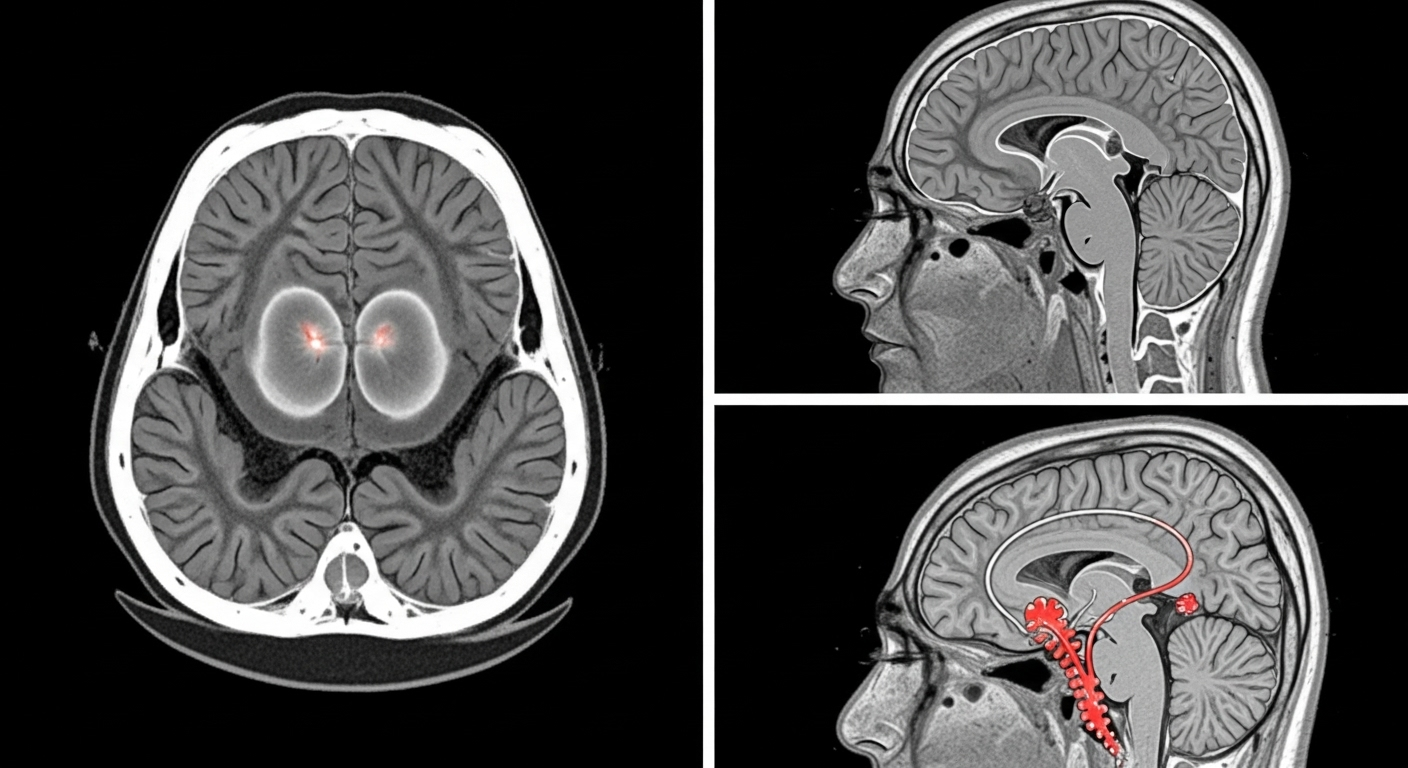

뇌졸중은 뇌혈관이 갑자기 막히거나 터지면서 뇌세포에 혈류 공급이 차단되는 응급 질환입니다.

크게 허혈성 뇌졸중(뇌경색)과 출혈성 뇌졸중(뇌출혈)로 나뉘며, 발생 시 빠른 대처가 생존과 회복을 좌우합니다.